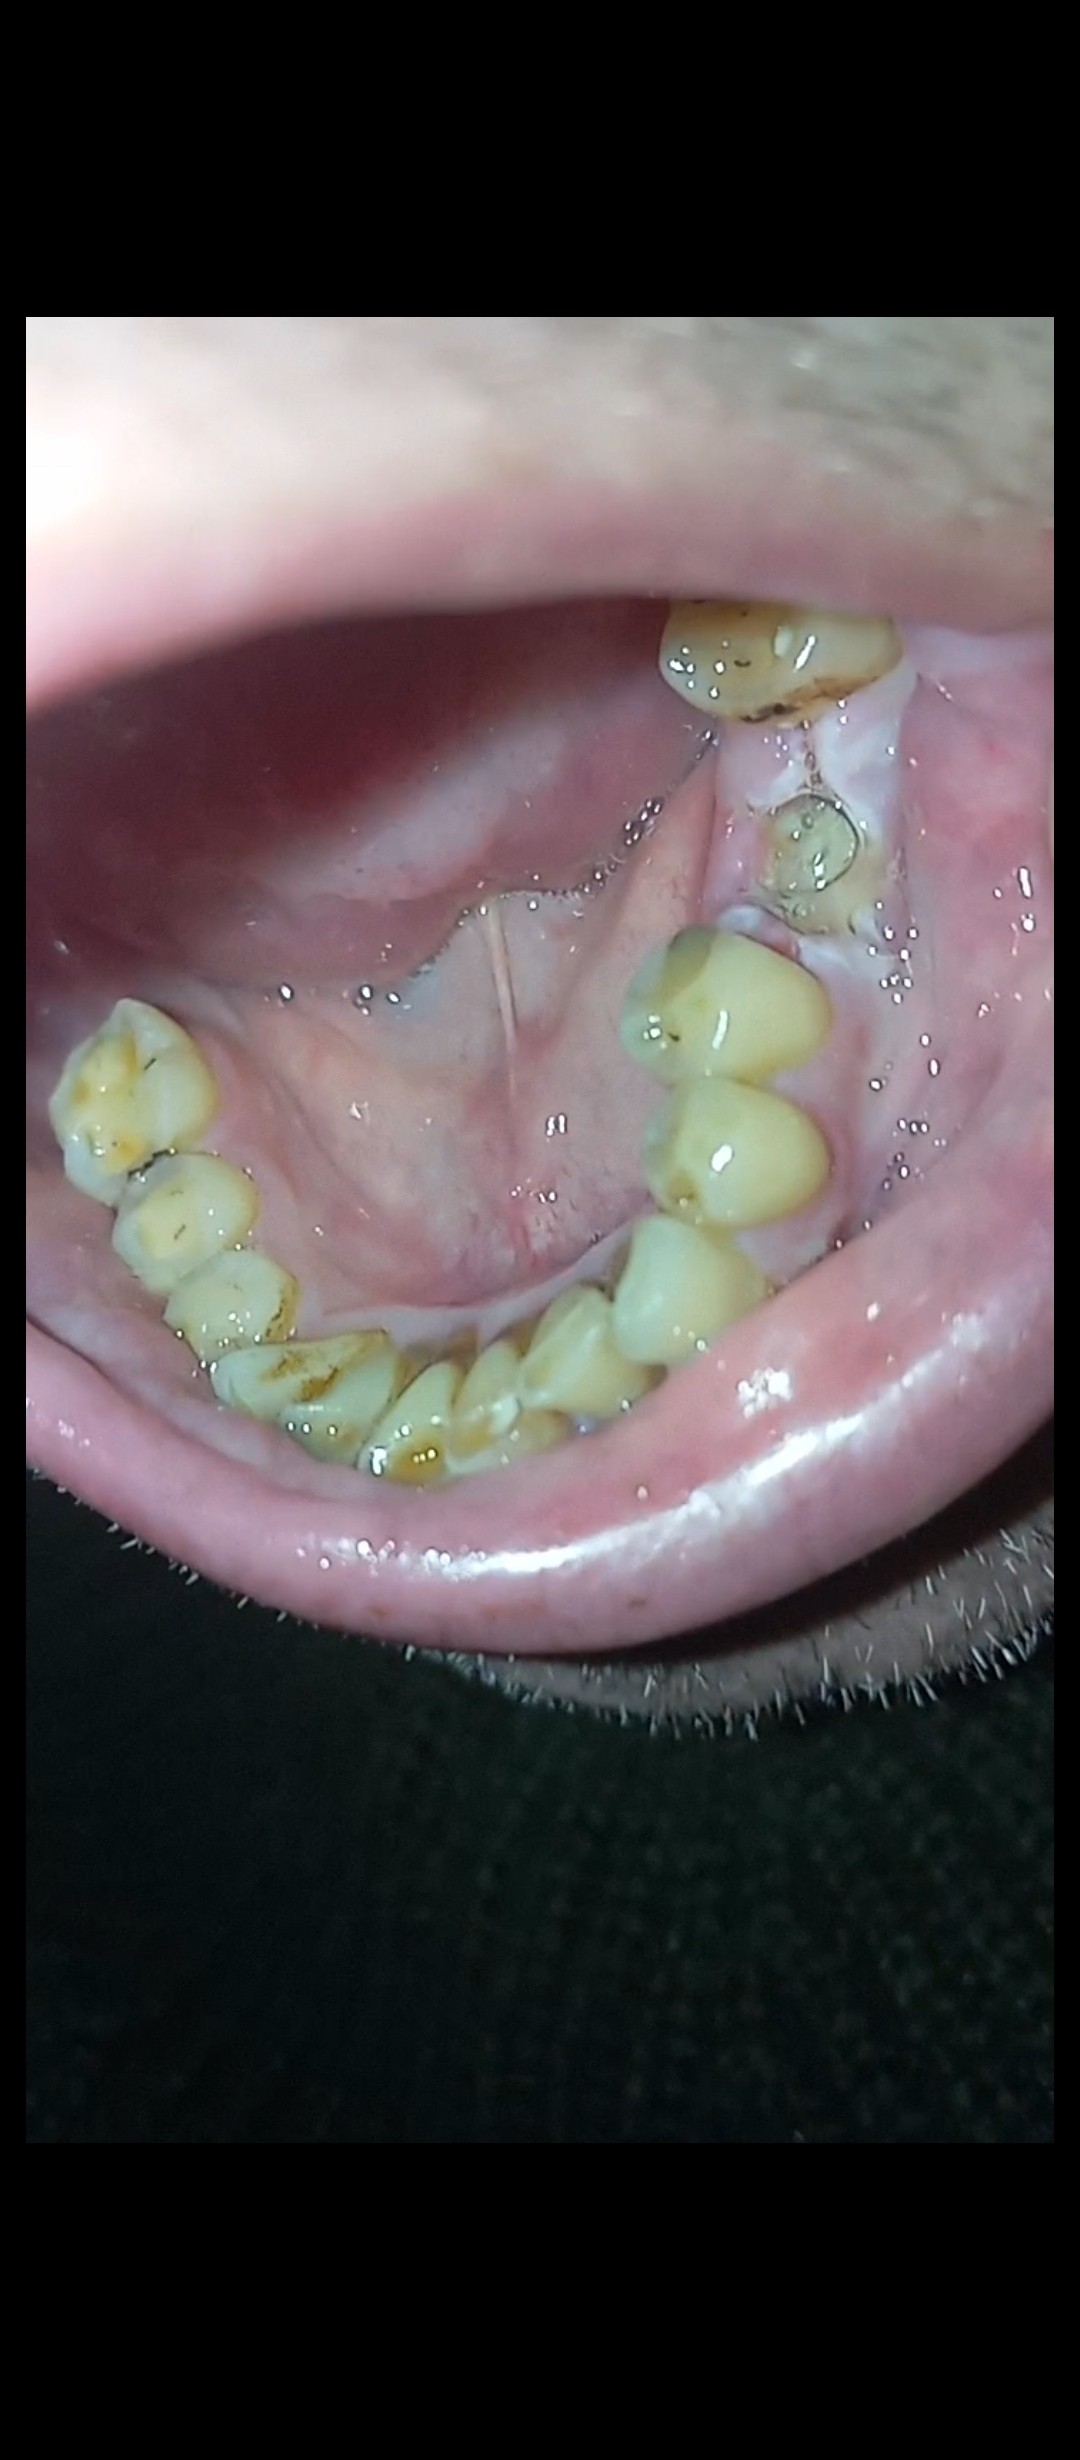

Вітаю, Добрый день. Неделю назад у меня начала болеть десна в нижнем ряду за седьмым зубом. Там как бы ранка Толи трещина и подпухло немного. Та восьмерка седит крепко. Мне 46 доктор говорил шо она уже не выйдет. Так вот через пару дней добавилась боль в шестом или седьмом зубе. Пульсирующая боль. Ночью не спал почти. Утром сегодня поехал к хирургу он удалил шестой зуб так как он плохой на снимке. Теперь я думаю решил ли я проблему, или это будет продолжаться и в е это из-за восьмёрки? Как думаете на снимке есть восполнение которое давало боль? Спасибо

"Теперь я думаю решил ли я проблему, или это будет продолжаться и в е это из-за восьмёрки? Как думаете на снимке есть восполнение которое давало боль? " - Есть воспаление, зуб удалили правильно. Но боль, которую вы испытывали, скорее всего, была связана с воспалением десны над восьмым зубом, так как всё от туда начиналось.

Я ещё не пойму что болит. Было сложное удаление. Там на снимке киста была на шестерка? А семёрка на снимке нормально?

"Там на снимке киста была на шестерка? " - Не киста, но гранулема, т. е. очаг хронического воспаления вокруг верхушки корня.

"А семёрка на снимке нормально? " - Да, нормально.